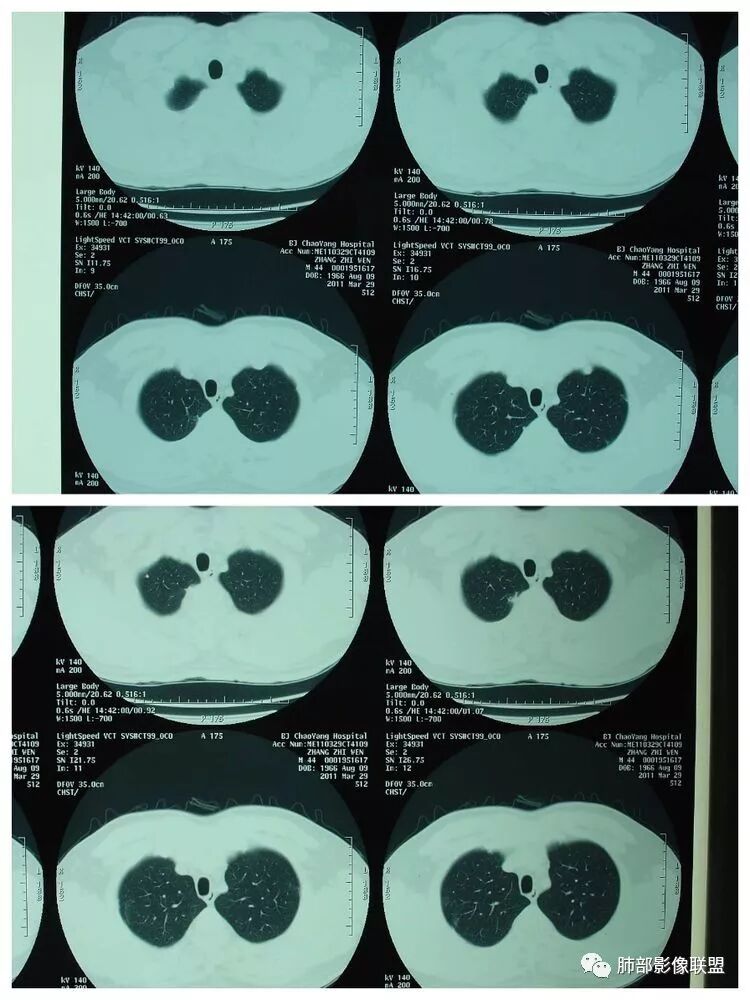

胸 CT

南边:胸膜下,类圆形,边界清,内有坏死,典型的反晕征,支气管壁增厚不明显,支持血道来源脓毒栓子所致梗死、感染

血道来源没问题

左下叶大片类似病灶

南边:反晕征是毛霉菌的特点按理单从影像:毛霉菌更多符合因为细菌性的特点:液气平面,囊,这个没出现

肺克的影像表现(唐绍宏总结):分布:单侧上叶病变,以右肺上叶多见;患者长期卧床则双脚下肺后基底段分布(国外下肺多见,可能与平均寿命长,卧床及住托老机构多有关) ;如多叶段病变,则以肺上叶后段或下叶后基底段为最明显形态:气管壁增厚、磨玻璃、小叶实变、节段实变、大叶实变,坏死小空洞(直径小于2cm) ,少量胸腔积液50%、脓胸20%特点:早期气管壁增厚较明显、广泛,越靠近病灶越明显,越靠近肺门越明显,见于实变病灶外,偶尔见于磨玻璃影内(支气管通气征) ;未经抗生素治疗,实变病灶内无支气管通气征;早期即可出现坏死,无论坏死还是空洞,绝大多数直径小于2cm (可能与此菌有厚夹膜有关,参考隐球菌)